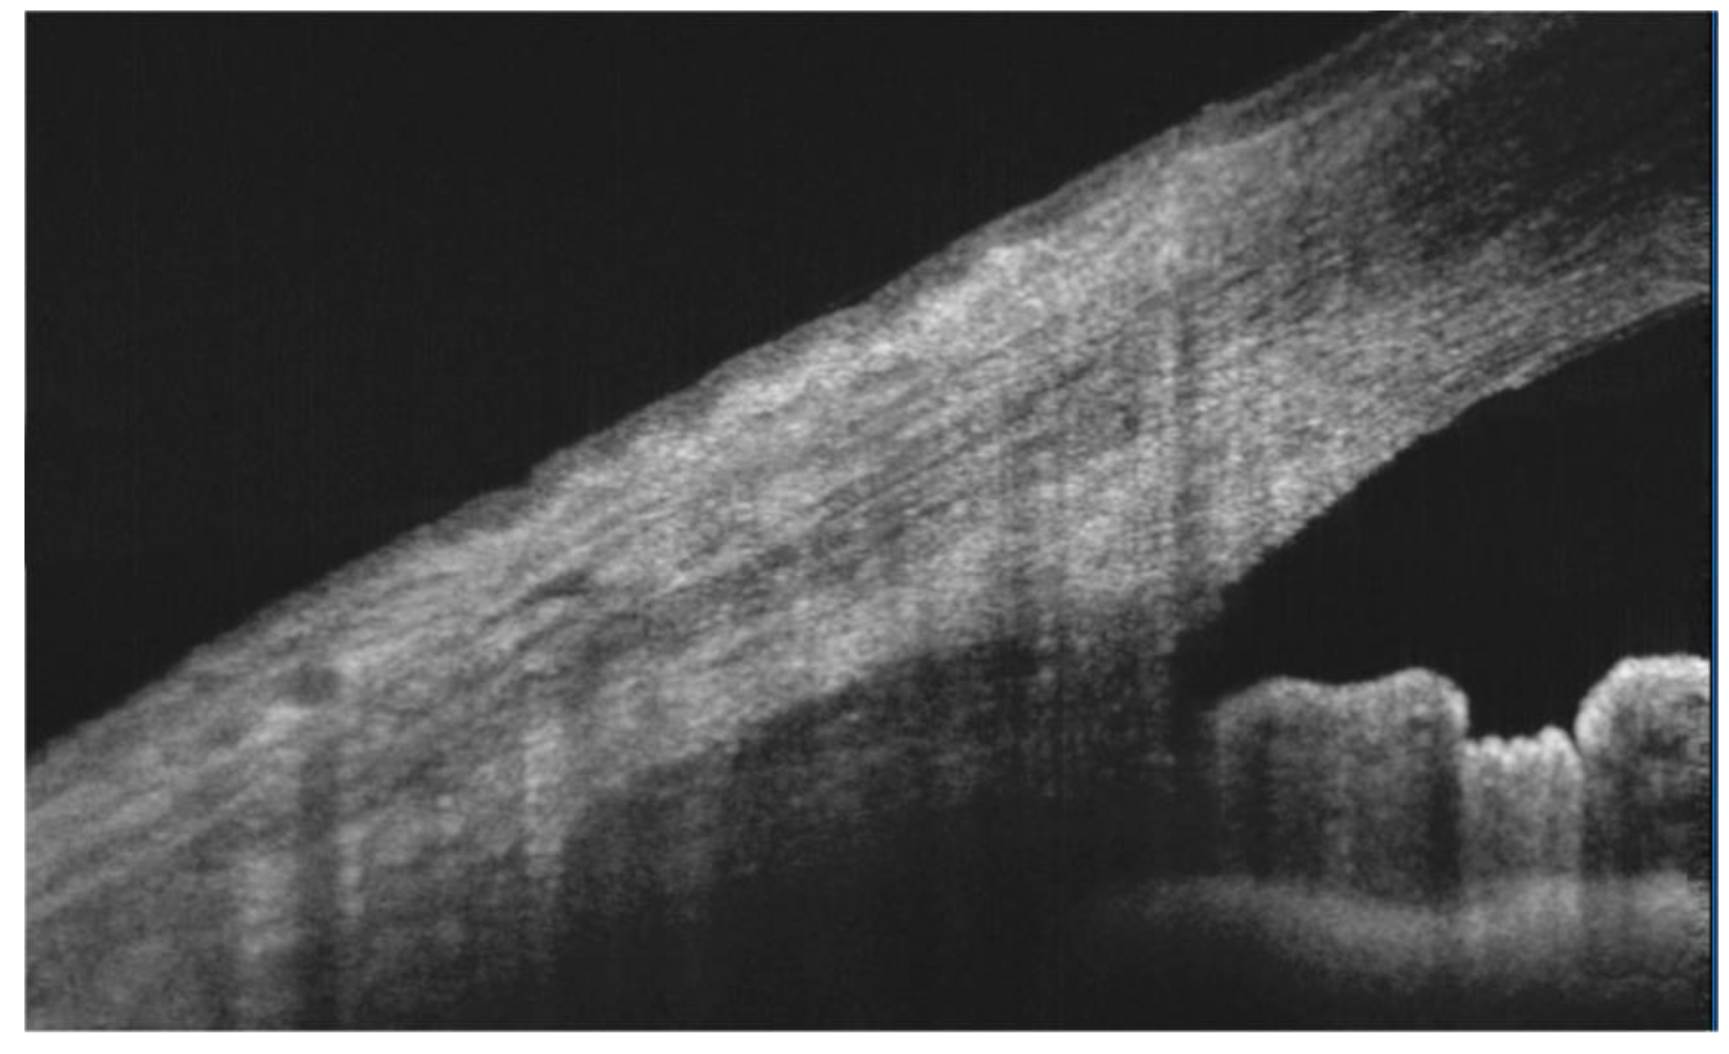

- Hwang, H.S.; Park, C.W.; Joo, C.K. Novel noncontact meibography with anterior segment optical coherence tomography: Hosikmeibography. Cornea 2013, 32, 40–43. [Google Scholar] [CrossRef]

- Hwang, H.S.; Shin, J.G.; Lee, B.H.; Eom, T.J.; Joo, C.K. In vivo 3D meibography of the human eyelid using real time imaging Fourier-domain OCT. PLoS ONE 2013, 8, 67143. [Google Scholar] [CrossRef]

- Liang, Q.; Pan, Z.; Zhou, M.; Zhang, Y.; Wang, N.; Li, B.; Baudouin, C.; Labbé, A. Evaluation of optical coherence tomography meibography in patients with obstructive meibomian gland dysfunction. Cornea 2015, 34, 1193–1199. [Google Scholar] [CrossRef]

- Yoo, Y.S.; Na, K.S.; Byun, Y.S.; Shin, J.G.; Lee, B.H.; Yoon, G.; Eom, T.J.; Joo, C.K. Examination of gland dropout detected on infrared meibography by using optical coherence tomography meibography. Ocul. Surf. 2017, 15, 130–138. [Google Scholar] [CrossRef]

- Napoli, P.E.; Coronella, F.; Satta, G.M.; Iovino, C.; Sanna, R.; Fossarello, M. A simple novel technique of infrared meibography by means of spectral-domain optical coherence tomography: A cross-sectional clinical study. PLoS ONE 2016, 11, e0165558. [Google Scholar] [CrossRef]